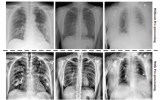

使用肺部X射線診斷COVID-19

2020年7月22日- 塞維利亞大學計算機工程學院(ETSII)計算機架構和技術系的研究人員正在研究一種使用患者肺部X射線圖像幫助診斷COVID-19的系統。 2020-07-24